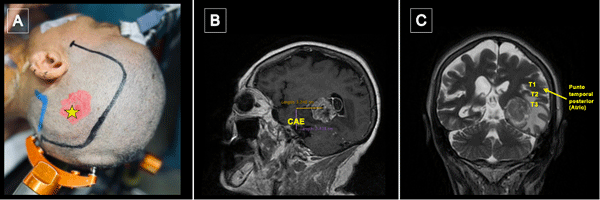

La incisión se centró en el punto temporal posterior (Figura 3), realizándose una herradura frontotemporooccipital izquierda y una cuidadosa hemostasia del colgajo. Craneotomía frontotemporal izquierda. La duramadre fue infiltrada con lidocaína al 1%. Posterior a ello se efectuó una durotomía arciforme con pedículo hacia basal exponiendo el giro temporal superior y medio. Con la paciente despierta se hizo ecografía intraoperatoria para delimitación de los márgenes tumorales, los cuales se identificaron con “tags” (Figura 4).

Figura 3.Punto temporal posterior, posicionamiento. A) Posicionamiento de la cabeza del paciente en cabezal de Mayfield Marcación de incisión centrada en punto temporal posterior (estrella amarilla). B) Se toma como referencia anatómica el conducto auditivo externo (CAE) para medición de punto temporal posterior. C) El punto temporal posterior corresponde topográficamente con el atrio del ventrículo lateral.

Figura 4. Ecografía intraoperatoria y mapeo cortical. A) Utilización de guía ecográfica intraoperatoria para identificar tumor y delimitar sus márgenes (A: Anterior; L: Lateral; M: Medial, P: Posterior). B) Marcación de los límites del tumor con tags de letras (A: Anterior; B: Medial; C: Posterior; D: Inferior) y de las áreas de mapeo positivo con presentación de anomia con dos tags de boca en región posterior de T2. Se expusieron también los giros temporales superior (T1), medio (T2) e inferior (T3) y se optó por corticotomía trans-T2.